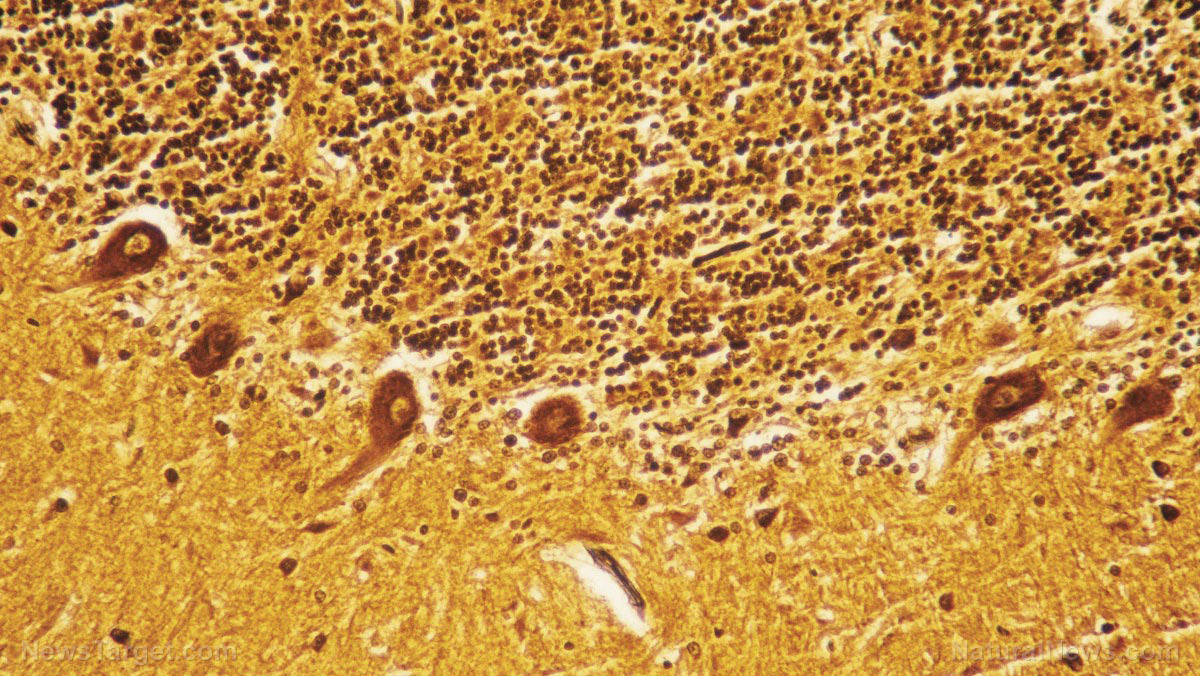

A controversial startup company is looking to harvest fresh human brains. The company is called Nectome and the founders are already preying upon the suicidal, the terminally ill and those who are willing to sacrifice their lives for "science." The company claims they can preserve your brain so it can be uploaded to the cloud in the future. In order for the company to stay in business, they must promote suicide, but with benefits. The technology uses a sophisticated embalming process to preserve a person’s brain so it can be uploaded to a data server in microscopic detail, synapse by synapse. The goal is to recreate a person’s brain, to potentially reconstruct memories, understand personalities, and relay wisdom from experiences. Nectome’s website asks, “What if we told you we could back up your mind?” The only catch is that the operation is fatal. The procedure requires fresh brains and will have to prey upon people with terminal illness or people seeking physician-assisted suicide. Nectome cofounder and MIT graduate Robert McIntyre will be pitching the idea to investors at YC’s “demo days.” The company has already been awarded a federal grant of nearly $1 million from the National Institute of Mental Health. Nectome’s founders have begun working with MIT neuroscientist Edward Boyden who has demonstrated a way to preserve a pig brain and detail every synapse on a computer model. Nectome’s founders have already demonstrated that their technique can work. They were able to preserve an elderly woman’s brain 2.5 hours after her death using aldehyde-stabilized cryopreservation. The procedure took roughly six hours and the brain was cut into paper-thin sheets so it could be imaged with an electron microscope. They effectively demonstrated they can preserve an entire brain at the nanometer level, detailing the entire web of synapses that connect neurons. By detailing this connectome, including billions of brain cells and the thousands of neurons that interact with one another, Nectome can bring a dead brain back to life again, in a computer. In this way, information can be retrieved from the brains of the deceased. In order for the procedure to work, the company must acquire fresh brains. In a state where euthanasia is legal, patients may elect to die so their brain can be preserved. A patient who is told they have an untreatable illness could elect to lay down on the operating table and have their brain pumped full of embalming chemicals. The suicidal patient would be hooked up to a heart-lung machine and put under general anesthesia, as the carotid arteries in their neck are pumped full of embalming fluids. The procedure would be legal in California, where the End of Life Option Act gives patients the option to choose physician-assisted suicide. Some people, afraid of being forgotten forever, will come to believe in the technology so they can be remembered in some way, shape, or form. A patient’s fear of death may be consoled if they believe that their brain was being preserved for a future time. The entire process is controversial, promising transhumanists a way to resurrect as avatars in computers while encouraging people to give up their lives in the name of science. Initiatives like these may also encourage healthcare providers to essentially give up on some patients in order to profit off their organ donation. There will be no reason to rescue or heal a patient if their brain donation is more profitable. The procedure is essentially a depopulation scheme. Nectome’s founders are even creating a waiting list for prospective customers. To join the list, customers must put down a fully refundable $10,000 deposit. At least twenty-five people have signed up. One of the prospective customers is a 32-year-old investor who believes that all brains will eventually be uploaded to the cloud in his lifetime. For more weird science news, visit WeirdScienceNews.com or MedicalViolence.com. Sources include: TechnologyReview.com Glitch.News